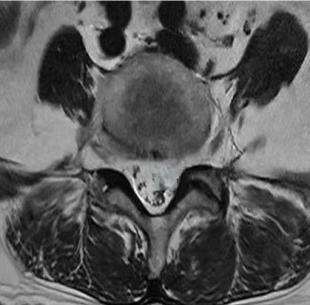

• 不同入路脊柱内镜手术治疗L4/5节段脱垂型腰椎间盘突出症的疗效比较

摘要:目的 观察经椎间孔入路内镜下腰椎间盘切除术(TELD)和经椎板间入路内镜下腰椎间盘摘除术(IELD)治疗L4/5节段脱垂型腰椎间盘突出症(LDH)的临床疗效。方法 回顾性分析2020年11月-2022年11月该院采用脊柱内镜手术治疗的75例L4/5节段脱垂型LDH患者的临床资料。根据手术入路的不同,将患者分为TELD组(53例)和IELD组(22例)。比较两组患者的手术情况和术后疗效。结果 与TELD组比较,IELD组的手术时间明显缩短,术中透视次数明显减少,差异均有统计学意义(P < 0.05);两组患者住院时间和并发症发生率比较,差异均无统计学意义(P > 0.05)。所有患者术后均获得12~19个月的随访。两组患者末次随访时的视觉模拟评分法(VAS)评分和Oswestry功能障碍指数(ODI)明显低于术前,且IELD组明显低于TELD组,差异均有统计学意义(P < 0.05)。按照突出物和神经根的不同位置进一步分析,两组肩上型患者(TELD组10例,IELD组6例)末次随访时的VAS评分和ODI明显低于术前,且IELD组末次随访时的VAS评分明显低于TELD组,差异均有统计学意义(P < 0.05);两组腋下型患者(TELD组8例,IELD组16例)末次随访时的VAS评分和ODI明显低于术前,且IELD组明显低于TELD组,差异均有统计学意义(P < 0.05);35例肩前型患者经TELD术后,末次随访时的VAS评分和ODI明显低于术前,差异有统计学意义(P < 0.05)。按照突出物的不同Lee分区进一步分析,两组Lee Ⅲ区患者(TELD组44例,IELD组10例)末次随访时的VAS评分和ODI明显低于术前,且IELD组的ODI明显低于TELD组,差异均有统计学意义(P < 0.05);两组Lee Ⅳ区患者(TELD组9例,IELD组12例)末次随访时的VAS评分和ODI明显低于术前,且IELD组明显低于TELD组,差异均有统计学意义(P < 0.05)。结论 采用TELD和IELD治疗L4/5节段脱垂型LDH,均可获得较满意的减压效果,但IELD的手术时间相对较短,X线透视次数较少,且对肩上型、腋下型、Lee Ⅲ区和Lee Ⅳ区的减压效果更有优势。